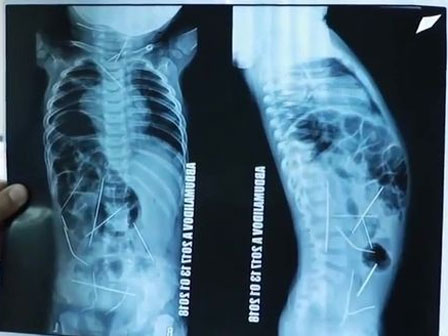

Trước đó, vào ngày 12/1/2018, Nhất Hàng đang đi học ở trường thì đột nhiên sốt cao, nôn mửa. Khi được đưa đến phòng y tế, em đã sốt cao đến 41,5 độ, nhà trường liền lập tức đưa em đến bệnh viện huyện Yên Lăng. Nhưng tình hình chuyển biến xấu, em có triệu chứng nói mớ, co giật, sốt cao, cuối cùng phải chuyển lên bệnh viện bệnh viện trực thuộc số 1 Trịnh Châu. Kết quả trận sốt này đã khiến cả gia đình em suy sụp. Nhất Hàng bị mắc bệnh não hoại tử cấp, cuống não, hạch nền, vùng dưới đồi não đều bị tổn thương.